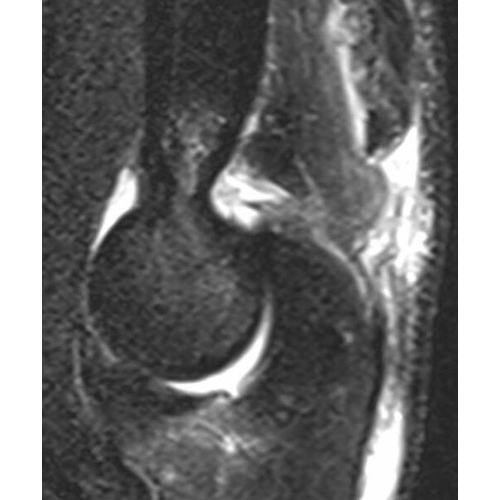

MRI Impression:

1. There is a bony avulsion of the triceps insertion from the olecranon which accounts for the bony fragments seen on preceding radiographs. There is retraction of the tendon stump 2.5 cm with surrounding edema.

2. There is a moderate to high-grade ulnar collateral ligament tear involving the distal attachments to the sublime tubercle of the ulna.

3. There is edema from a bone contusion in the coronoid process of the ulna without evidence of displaced fracture at that site. Case Photo #2 and Case Photo #3